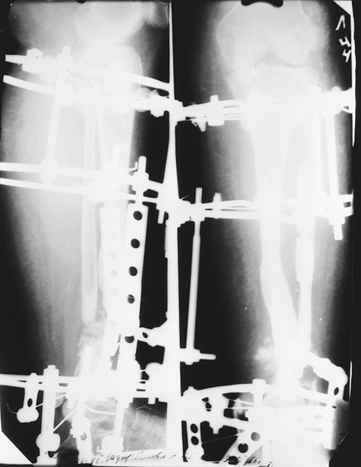

Случай, который я представляю, был сделан мной около 20 лет назад в Кургане.

Женщина 28 лет, пошедшая 13 предыдущих оперативных вмешательств по-поводу ВПБ имела 9 см. укорочения.

На первом этапе аппаратом Илизарова закрыто устранена деформация голени.

На втором этапе произведёно освежение краёв костных фрагментов б/б и м/б костей с приданием проксимальному фрагменту б/б кости впалой, а дистальному выпуклой формы, открытие канала проксимального фрагмента и погружной остеосинтез, а также остеотомия б/б кости в в/3 и м/б кости на границе с/3 и н/3 голени. Больной проводился одновременный бифокальный компрессионно-дистракционный остеосинтез. Достигнуто 11 см. удлинение и сращение ВПГ.

Срок лечения 11 месяцев. Наблюдение 2 года.

С уважением!